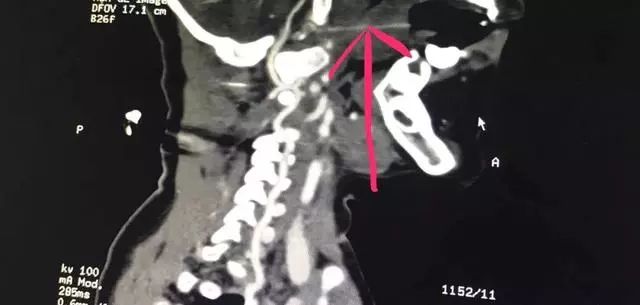

接诊的医护人员迅速为患儿安排了病床并实施了相关检查。CTA检查、颅脑CT、三维重建等一系列检查显示,长达13厘米的竹签经过小姑娘的口腔,直指环枢椎关节间隙,紧紧抵住人体最致命部位之一的椎动脉。

患儿的影像资料印证了医务部孔心涓主任的担心:

竹签刺入的部位极其特殊而凶险,如果竹签有一丁点挪动,可能会导致椎动脉被刺破,患儿就会有生命危险。